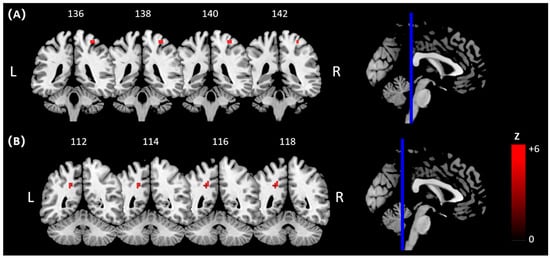

| Comparisons | Brain Regions/BA | Peak MNI Coordinates | Cluster Voxels | Peak Z Values | |||

|---|---|---|---|---|---|---|---|

| x | y | z | |||||

| Pre-hitting | Golf group > Control group | R Insula/BA 48 | 39 | 15 | 0 | 67 | 3.90 a |

| R Posterior Cingulate Cortex (PCC)/BA 17 | 18 | −60 | 12 | 69 | 3.85 a | ||

| Hitting | Golf group > Control group | R Cerebelum/BA 19 | 18 | −57 | −27 | 99 | 4.36 a |

| L Postcentral Gyrus/BA 2 | −36 | −39 | 57 | 105 | 4.26 a | ||

| R Postcentral Gyrus/BA 2 | 27 | −39 | 66 | 255 | 4.04 a | ||

| Golf group < Control group | R Cerebellum/BA 18 | 12 | −72 | −15 | 114 | 4.05 a | |

| Hitting > Pre-hitting | Golf group < Control group | L Postcentral Gyrus/BA 2 | −36 | −39 | 57 | 175 | 4.54 a |

| R Postcentral Gyrus/BA 4 | 33 | −33 | 66 | 199 | 4.06 a | ||